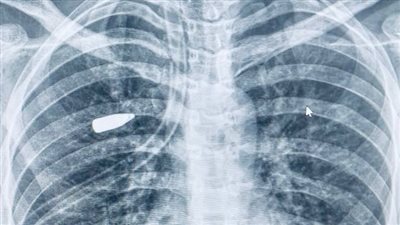

تمكن فريق طبي بقسم جراحة التجميل بالمستشفى الرئيسي بجامعة أسيوط من إجراء عملية تكميم معدة بالمنظار الجراحي بنجاح لطفلة تبلغ من العمر 14 عاما، كانت تعاني من سمنة مفرطة بمؤشر كتلة جسم (BMI) بلغ 80.